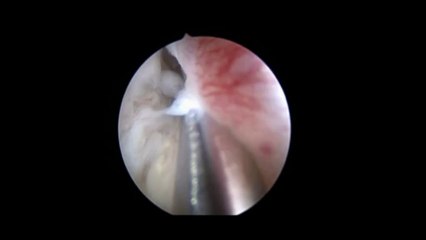

Laparoskopi ile Endometiroma 32 - Prof. Dr. Aydan Biri

Laparoskopi ile Endometiroma 32 - Prof. Dr.